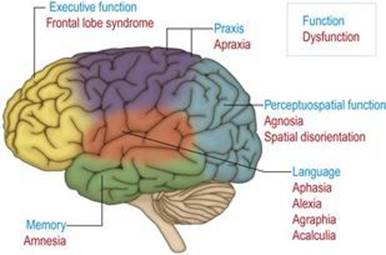

عملکردهای عصب روانشناختی

کارکردهای عصب روانشناختی زبان، ادراک، تحلیل فضایی، حرکات ماهر آموخته شده، حافظه و حل مسئله (یا کارکردهای اجرایی) در نیمکرههای مغزی سازماندهی میشوند (شکل ۱.۴۲). بر این اساس، ضایعات ساقه مغز، مخچه و نخاع با نقص روانی همراه نیستند. سازماندهی عملکردهای عصب روانشناختی در نیمکره مغز مانند سیستم حرکتی و حسی بسیار محلی است.

شکل ۱.۴۲ محلی سازی عملکردهای عصبی روانشناختی در نیمکره مغزی و سندرمهای مرتبط با اختلال عملکرد.

شکل ۱.۴۲ محلی سازی عملکردهای عصبی روانشناختی در نیمکره مغزی و سندرمهای مرتبط با اختلال عملکرد.

کارکردهای زبان (گفتار، خواندن، نوشتن و محاسبه) در نواحی لوبهای پیشانی، جداری و تمپورال مجاور شکاف جانبی چپ، به اصطلاح”ناحیه زبان“سازماندهی میشوند. در حالی که فرآیندهای بصری اولیه در لوبهای پس سری سازماندهی میشوند، ادراک یا تشخیص اشیاء و چهرههای انسان به صورت پیشبینی به لوبهای زمانی مغز سازماندهی میشود. توانایی فضایی جهت حرکت اندامها و بدن در فضا (عملکرد دیداری فضایی) از طریق برآمدگی به لوبهای جداری سازماندهی میشود. نواحی پیش حرکتی لوبهای فرونتال، از جمله ناحیه حرکتی تکمیلی که در قسمت داخلی نیمکره قرار دارد، بر اجرای حرکات آموخته شده و ماهرانه سر، گردن و اندامها حاکم است (پراکسیس). ساختارها در جنبههای داخلی لوبهای تمپورال، بخشی از سیستم لیمبیک، مسئول یادگیری اطلاعات جدید و یادآوری از تجربه (حافظه) هستند. سازماندهی رفتار شامل حل مسئله و دستیابی به رفتار هدفمند (عملکرد اجرایی) در نواحی پیش پیشانی لوبهای فرونتال سازماندهی میشود.

از این همبستگیهای عصبی-روانشناختی و تشریحی استنباط میشود که ضایعات ناحیه زبان منجر به از دست دادن گفتار (آفازی)، خواندن (الکسی)، نوشتن (آگرافیا) و محاسبه (acalculia) میشود، در حالی که ضایعات قشر گیجگاهی منجر به از دست دادن میشود. ادراک (آگنوزیا) و جهت گیری فضایی (بی جهتی فضایی). از دست دادن دانش حرکات ماهر آموخته شده (آپراکسی) به دنبال ضایعات قشر پیش حرکتی است. اختلالات دو طرفه لوبهای تمپورال داخلی و سیستم لیمبیک منجر به از دست دادن عملکرد حافظه میشود (فراموشی). آسیب به قشر جلوی مغز منجر به اختلال رفتاری مشخص همراه با از دست دادن پیشاندیشی، برنامهریزی و عاطفه مناسب میشود، که در تغییر شخصیت و رفتار آشکار میشود (لوب فرونتال یا سندرم نارسا اجرایی).